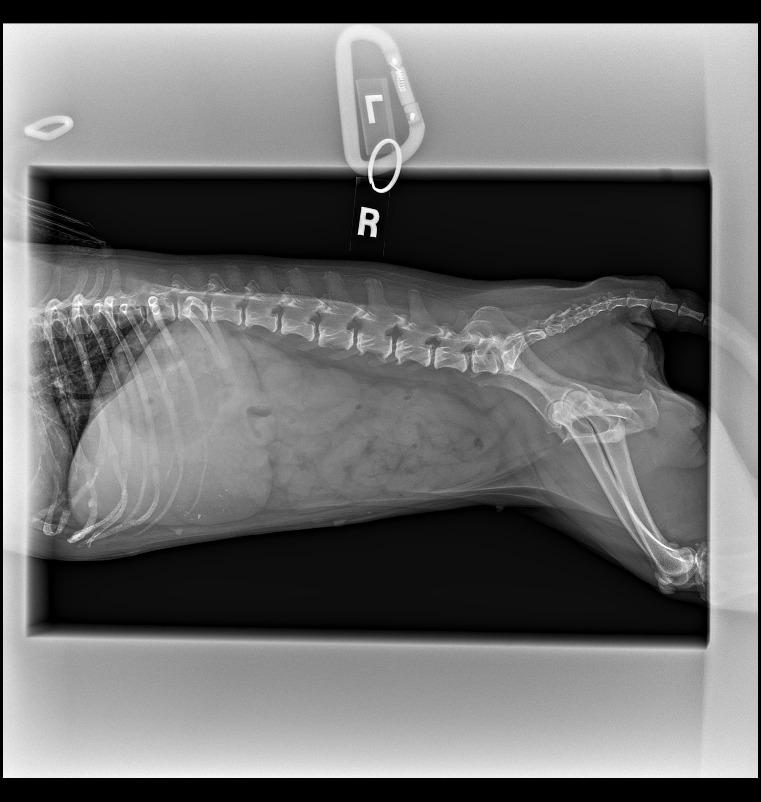

Meet Snubble, a sweet and resilient 9.5-year-old girl who's been through a lot, but still has so much love to give. Snubble was originally confiscated from a hoarding situation and ended up spending a full year at a city shelter while legal proceedings dragged on. Once she was finally released, she came to us -- and has now been with us for a year and a half as we've worked through her medical needs.<br/><br/>Snubble has a chronic gastrointestinal condition (IBS) that causes ongoing digestive issues. She'll always have soft stool and some straining, and her condition flares with stress and certain foods. It's managed with daily medication and a very specific diet, and while it's a lifelong condition, she's been doing much better with consistent care. Her future adopter will need to be prepared to continue that routine and keep her stable and comfortable.<br/><br/>Despite all of this, Snubble is a truly wonderful dog. She's incredibly affectionate and loves to snuggle up with her people. She gets along well with other dogs of all energy levels and has a very mellow, gentle personality. A calm home where she can truly relax would be ideal for her.<br/><br/>Snubble has been through more than most dogs ever should, but she remains full of love and trust. What she really needs now is a calm, caring home where she can finally exhale and feel safe. Snubble has waited a long time for her happy ending. She's been overlooked again and again, simply because her care requires a little extra effort. But we promise, she is so worth it. She will fill your home with soft snuggles and deep, grateful love. If you're the kind of person who believes in second chances and sees beauty in imperfection, Snubble just might be your perfect match. Please inquire today to learn more about giving her the loving home she's been waiting for!

Snubble has a chronic gastrointestinal condition (IBS) that causes ongoing digestive issues. She'll always have soft stool and some straining, and her condition flares with stress and certain foods. It's managed with daily medication and a very specific diet, and while it's a lifelong condition, she's been doing much better with consistent care. Her future adopter will need to be prepared to continue that routine and keep her stable and comfortable.